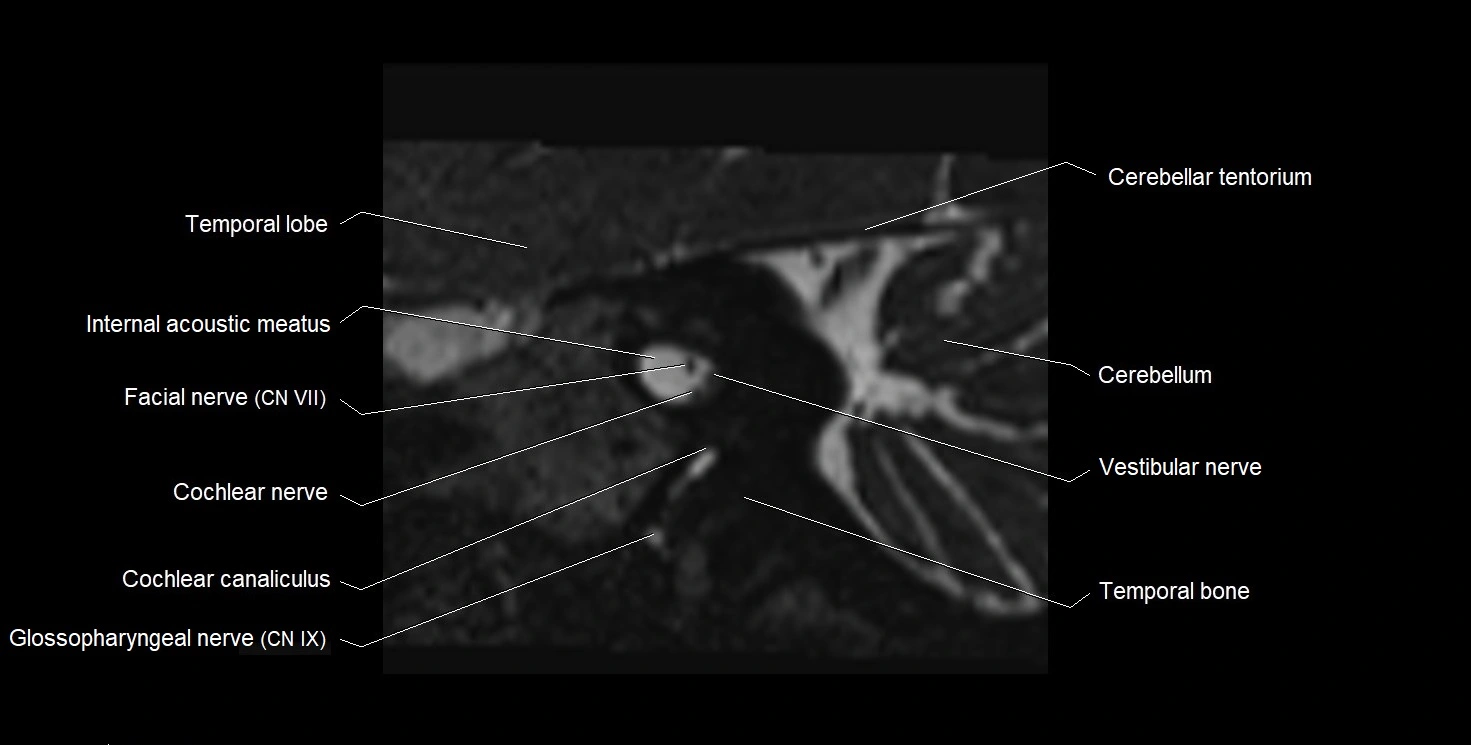

MRI Appearance

• The abducens nerve is a small, thin, linear structure

• Best visualized on high-resolution T2-weighted 3D MRI sequences (e.g., FIESTA or CISS)

• Seen as a hypointense (dark) line running from the brainstem at the pontomedullary junction, traversing the prepontine cistern, and entering Dorello’s canal under the petrosphenoidal ligament, then into the cavernous sinus, and finally the orbit

• May be challenging to visualize in standard MRI due to its small size

• Pathology may be inferred by absence, displacement, or enhancement of the nerve